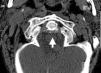

Axial skeleton affection due to chondrocalcinosis has been associated to calcium deposits in the intervertebral disc, the yellow ligament, the fact joints and even the sacroiliac joints. Calcification of the transverse ligament of the atlas (Figs. 1–3) is an infrequent manifestation and has been denominated the Crown Dens syndrome. It mostly constitutes an asymptomatic clinical picture but may be associated with episodes of acute cervical pain, stiffness and fever, with the added diagnostic difficulties of these cases.

X-ray studies show cervical spondyloarthritis and calcification of the transverse ligament of the atlas and winged ligaments of the atlas-axis joint (Fig. 4).

The Crowned Dens syndrome was described initially in 1985 by Bouvet et al.1,2 Diagnosis is based on the association of a compatible clinical picture and imaging findings, mainly calcium deposits in atlas-axis joint ligaments, visible on CT.3,4